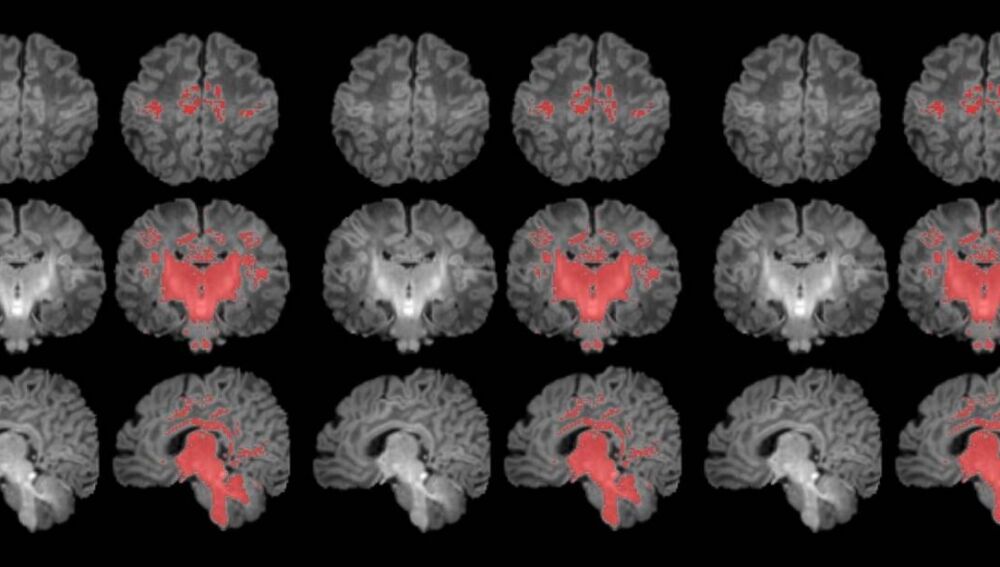

Resonancia magnética en el primer mes de vida

Para llevar a cabo el estudio se reclutó a mujeres embarazadas en seguimiento en el Hospital Clínic Barcelona, el Hospital de Sant Pau y el Hospital Sant Joan de Déu. Se monitorizaron los niveles de contaminantes atmosféricos a los cuales estaban expuestos durante la gestación y, después del parto, se seleccionó a 132 recién nacidos. A estos se les realizó una resonancia magnética antes de cumplir el primer mes de vida para observar el grado de maduración cerebral según sus niveles de mielinización.

Los resultados muestran una correlación clara entre una mayor exposición materna a PM2.5 durante el embarazo y una menor mielinización en el cerebro de los recién nacidos.